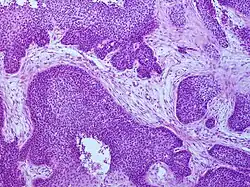

Medical history, physical examination and medical imaging may suggest a squamous-cell carcinoma, but a biopsy for histopathology generally establishes the diagnosis. TP63 staining is the main histological marker for squamous-cell carcinoma. In addition, TP63 is an essential transcription factor to establish the identity of the squamous cells.[18]